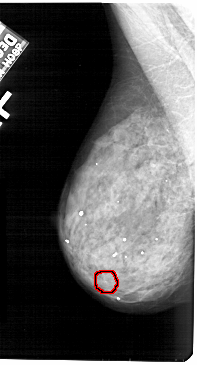

A_1420_1.LEFT_MLO

FILE: A_1420_1.LEFT_MLO.OVERLAY

TOTAL_ABNORMALITIES 1

ABNORMALITY 1

LESION_TYPE CALCIFICATION TYPE AMORPHOUS DISTRIBUTION CLUSTERED

ASSESSMENT 4

SUBTLETY 2

PATHOLOGY BENIGN

TOTAL_OUTLINES 1

BOUNDARY